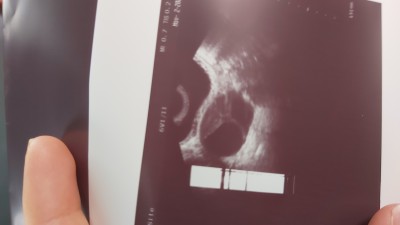

Merhaba kızlar yumurta toplama işlemim oldu 2 tane yumurtam donduruldu . Bu ay transfer olacaktı normalde ama rahmin iyi görünmüyor diye aya kalsın dedi doktorum bu şekil olan var mı yumurtalarin da büyük hala dedi

Senindemi attığım fotodaki gibiydi yumurtaların

Benim çok daha vahimdi yumurtaların aşırı gelismesi diyelim